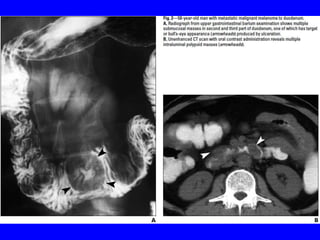

• Metastatic gastric &duodenal melanomas classically appear as small

submucosal nodules that may have central ulceration well-known

“target or bull’s-eye lesions” on endoscopy.

• These lesions may be either pigmented or amelanotic.

• The SI involvement with metastatic tumors is more common in

melanoma than upper or lower GIT due to its rich blood supply&

appear as intraluminal masses or serosal implants, usually

diagnosed on imaging studies.